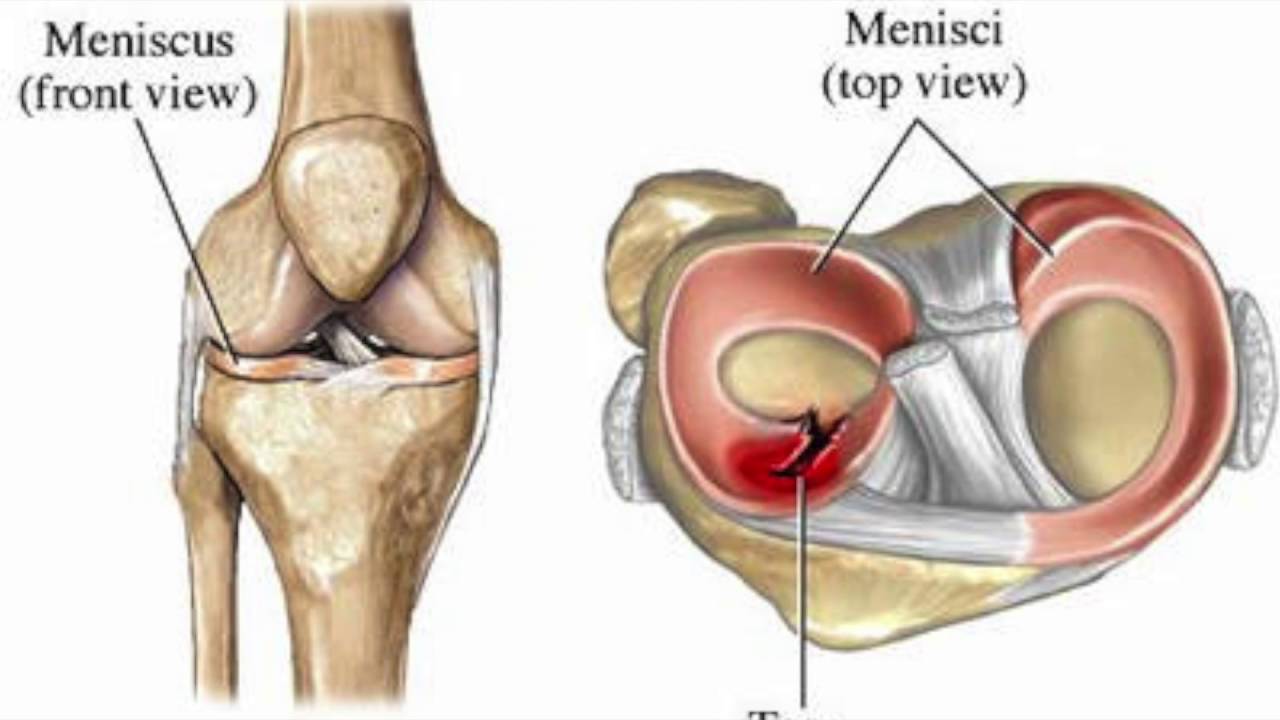

Анатомические изображения менисков и коленного сустава

Раздел: Иллюстрированные советы